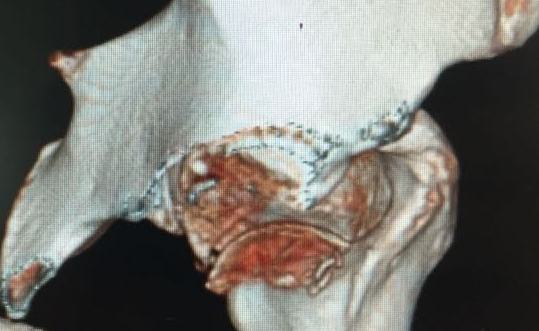

[Ortho] Pipkin II

Стоило ли заниматься остеосинтезом в этом случае?

Мужчина, 50 лет, активный, падение с высоты. При поступлении вправление

вывиха, других повреждений нет Без значимой сопутствующей патологии, не

курит. Стоило ли выполнять остеосинтез при таком оскольчатом переломе

или сразу пойти на ТНА?